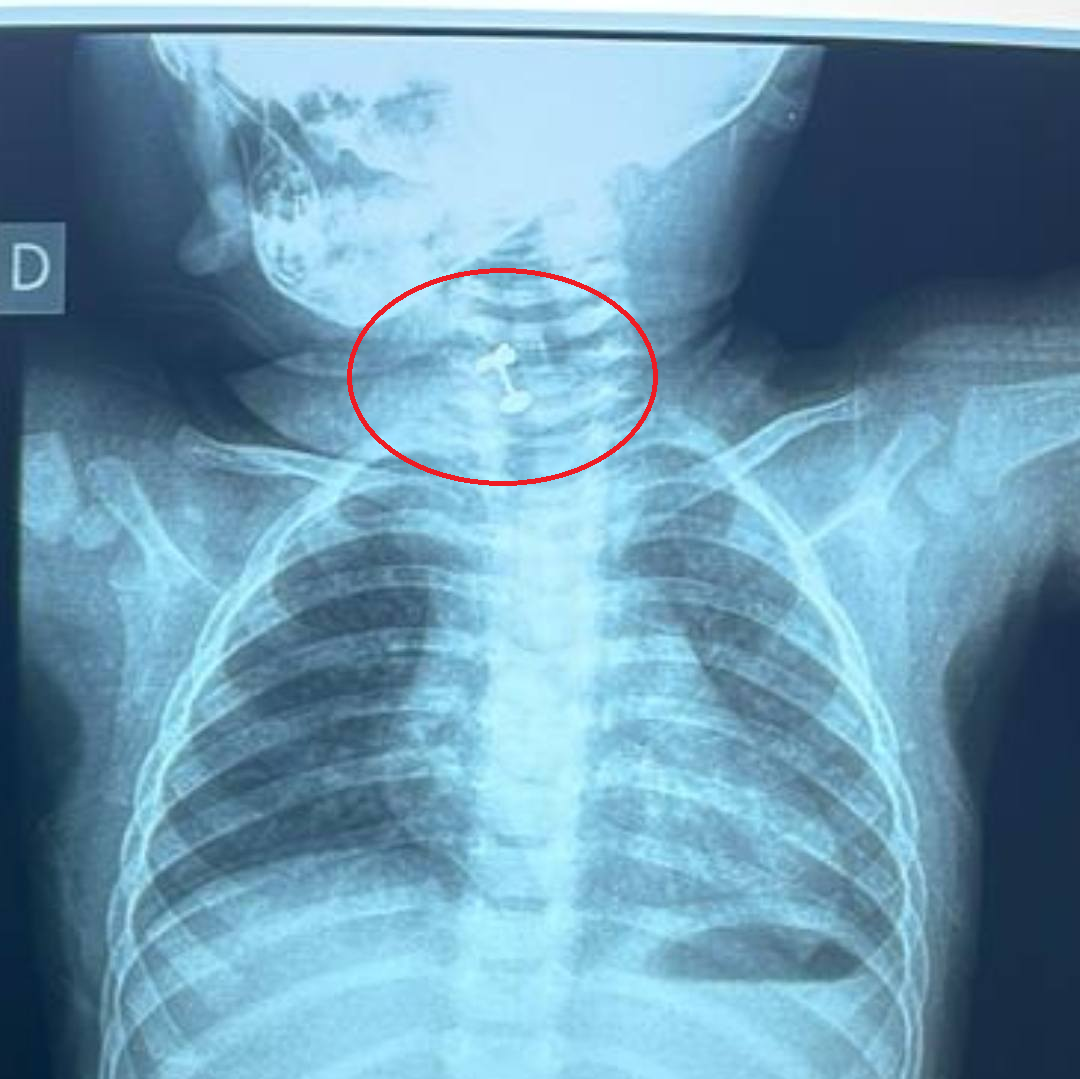

A través de sus redes sociales, el Dr. Carlos Morínigo, especialista en neumología, dio a conocer el caso de una beba de tan solo 10 meses que estuvo a punto de morir asfixiada luego de tragar su arito.

Ya en el Ineram, la niña, con franca dificultad respiratoria y sonidos de obstrucción parcial, ingresa a quirófano, donde los médicos detectaron el arito obstruyendo casi totalmente la laringe.

Ante la gravedad del caso, procedieron a la extracción inmediata del objeto. El Dr. Morínigo resaltó que, afortunadamente, el procedimiento fue un éxito y se logró extraer el arito.